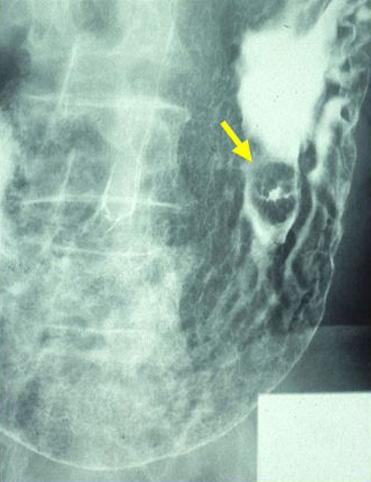

疾病(病理主体)的分类恶性淋巴系肿瘤/恶性淋巴瘤

部位(按器官分)胃(部位)/体部

检查方法X线

肿瘤的肉眼分类0型(表在型)/IIa型(IIa+IIc)

肿瘤最大直径15~19

肿瘤的深度sm